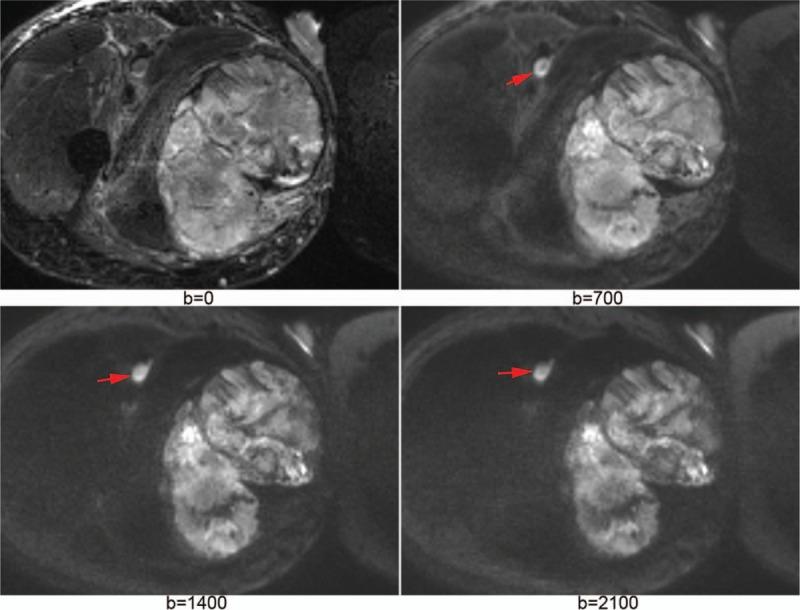

To investigate the feasibility of intravoxel incoherent motion (IVIM) diffusion-weighted imaging (DWI) and diffusion kurtosis imaging (DKI) in discriminating soft tissue sarcoma from vascular anomalies.Twenty-two patients with lower extremity soft tissue sarcoma and 15 patients with lower extremity vascular anomalies underwent IVIM-DWI and DKI. IVIM model generated true diffusion (D), perfusion fraction (f), and pseudo-diffusion coefficient (D). DKI model generated mean kurtosis (MK) and mean diffusion (MD). These parameters were measured by 2 radiologists separately through drawing region of interest. Intraclass correlation coefficient (ICC) was calculated to evaluate the inter-reader viability in measurement. The Mann-Whitney test was used to compare the parameters between vascular anomalies and soft tissue sarcoma. Receiver operating characteristic curves were constructed for assessing diagnostic accuracies.ICC was more than 0.8 for apparent diffusion coefficient (ADC), D, D, f, MK, and MD. Mean ADC, D, and MD were significantly lower in soft tissue sarcoma versus vascular anomalies (P < .05). Mean D and f were not significantly different (P > .05). Soft tissue sarcoma had significantly higher MK than vascular anomalies (P < .05). Areas under curve for ADC, D, MK, and MD were 0.876, 0.885, 0.894, and 0.812, respectively.IVIM and DKI are feasible in discriminating soft tissue sarcoma from vascular anomalies.